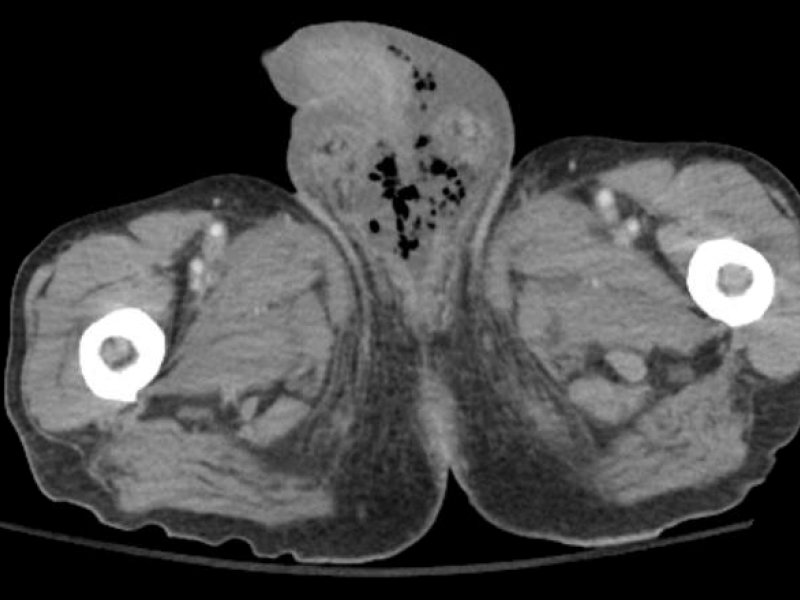

Answer: B) Fournier's Gangrene. Diagnosis: Fournier's

Imaging Case: 74 Year Old Male with Rectal Pain and Fatigue

Case: A 74 yo male patient with a PMH significant for rectal